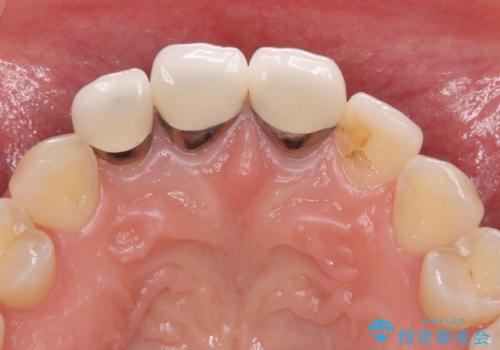

前歯の審美歯科治療 オールセラミッククラウンと部分矯正

- 上の前歯のセラミッククラウンが古くなったことと、下の前歯のデコボコを気にして来院された患者様です。

前歯は一部根管治療を行った後にオールセラミッククラウンに補綴することとしました。

補綴治療に先立ち、下顎前歯の部分矯正を行い、前歯の咬み合わせの安定性向上を図りました。